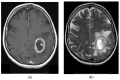

Glioblastoma, the most aggressive and common malignant primary brain tumour, is characterized by infiltrative growth, abundant vascularization, and aggressive clinical evolution. Patients with glioblastoma often face poor prognoses, with a median survival of approximately 15 months. Technological progress and the subsequent improvement in understanding the pathophysiology of these tumours have not translated into significant achievements in therapies or survival outcomes for patients. Progress in molecular profiling has yielded new omics data for a more refined classification of glioblastoma. Several typical genetic and epigenetic alterations in glioblastoma include mutations in genes regulating receptor tyrosine kinase (RTK)/rat sarcoma (RAS)/phosphoinositide 3-kinase (PI3K), p53, and retinoblastoma protein (RB) signalling, as well as mutation of isocitrate dehydrogenase (IDH), methylation of O6-methylguanine-DNA methyltransferase (MGMT), amplification of epidermal growth factor receptor vIII, and codeletion of 1p/19q. Certain microRNAs, such as miR-10b and miR-21, have also been identified as prognostic biomarkers. Effective treatment options for glioblastoma are limited. Surgery, radiotherapy, and alkylating agent chemotherapy remain the primary pillars of treatment. Only promoter methylation of the gene MGMT predicts the benefit from alkylating chemotherapy with temozolomide and it guides the choice of first-line treatment in elderly patients. Several targeted strategies based on tumour-intrinsic dominant signalling pathways and antigenic tumour profiles are under investigation in clinical trials. This review explores the potential genetic and epigenetic biomarkers that could be deployed as analytical tools in the diagnosis and prognostication of glioblastoma. Recent clinical advancements in treating glioblastoma are also discussed, along with the potential of liquid biopsies to advance personalized medicine in the field of glioblastoma, highlighting the challenges and promises for the future.